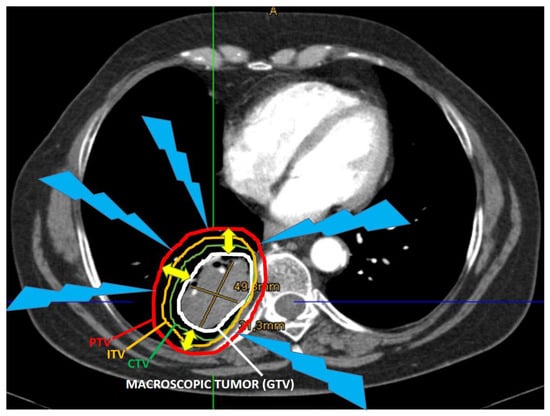

- Tang, C.; Liao, Z.; Gomez, D.; Levy, L.; Zhuang, Y.; Gebremichael, R.A.; Hong, D.S.; Komaki, R.; Welsh, J.W. Lymphopenia association with gross tumor volume and lung V5 and its effects on non-small cell lung Cancer patientoutcomes. Int. J. Radiat. Oncol. Biol. Phys. 2014, 89, 1084–1091. [Google Scholar] [CrossRef]

- Tubin, S.; Khan, M.K.; Salerno, G.; Mourad, W.F.; Yan, W.; Jeremic, B.; Tubin, S. Mono-institutional phase 2 study of innovative Stereotactic Body RadioTherapy targeting PArtial Tumor HYpoxic (SBRT-PATHY) clonogenic cells in unresectable bulky non-small cell lung cancer: Profound non-targeted effects by sparing peri-tumoral immune microenvironment. Radiat. Oncol. 2019, 14, 1–11. [Google Scholar] [CrossRef]